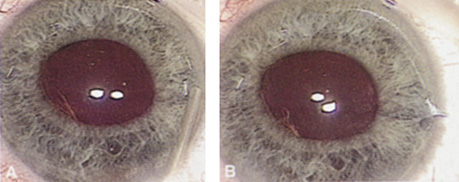

ENDOTHELIAL CELL COUNT.

Although slit-lamp examination can give the ophthalmologist an excellent estimate of endothelial health, sometimes a formal assessment of the corneal endothelial cell density is helpful (Fig. 4). This information is most likely to be helpful in advising patients who may be at greater risk of postoperative corneal decompensation. Specifically, patients with cornea guttata, previous ocular surgery, history of blunt ocular injury,56 exfoliation syndrome,57 iridocorneal-endothelial syndromes,58 or a history of glaucoma59 are known to have reduced endothelial cell counts. Patients with a history of acute angle closure are at particular risk because each episode of elevated intraocular pressure can damage endothelial cells.60

There are qualitative and quantitative methods for endothelial cell evaluation. Cell density can be measured directly with an endothelial cell camera. The surgeon also should view the photograph and qualitatively estimate the regularity of the endothelial cell mosaic. Some instruments calculate a coefficient of variability and percent of hexagonal cells.

When an endothelial cell camera is not available, qualitative assessment of count and cell morphology can be accomplished at the slit-lamp using a technique called specular reflection.61 The ophthalmologist focuses a narrow parallelepiped on the corneal epithelium, directing the beam at the periapical cornea from a 45-degree angle. The slit beam is moved slowly from side to side until the bright corneal reflex strikes the examiner's view from the epithelial surface reflection (first Purkinje-Sanson image). On high magnification, the examiner should focus on the endothelial surface just next to the bright reflex. The image of the endothelial mosaic will come into view. The surgeon can make a qualitative assessment of the cell density and degree of regularity. With practice, these estimates can be surprisingly accurate.